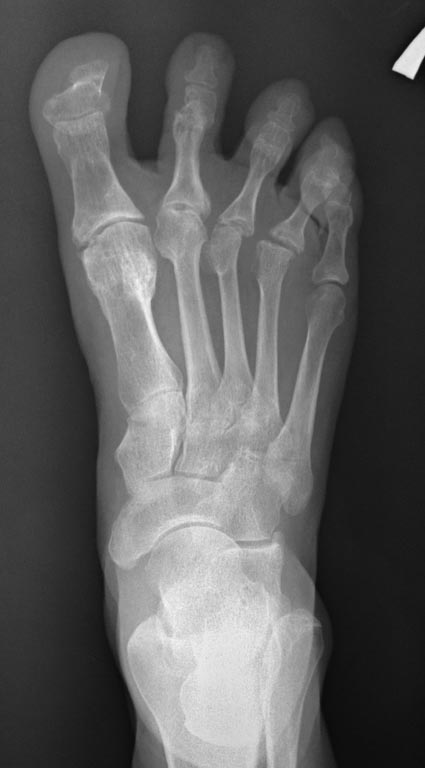

Пциентка Н, 58 лет. Больна с 2005г. Лечилась консервативно. Со слов, тогда было сильное искривление 1,2,3,4 пальцев в латеральную сторону.

В 2012г. операция: коррекция деформаций 1,2,3, 4 пальцев.Рецидив. В 2013г. – коррекция деформации 2,3,4 пальцев. С ноября 2014г. рецидив деформации 1,2,3,4 пальцев. Возможные варианты коррекции?

А что беспокоит пациентку? Есть ли натоптыши на подошве? Болит ли первый плюснефаланговый сустав? Или еще где болит? Лечим ведь пациента, а не деформацию. Если же исходить из имеющихся данных и отсутствия информации о ранее выполненных операциях, то необходимо выполнить обратную остеотомию Akin, чтобы устранить hallux varus; укорачивающие остеотомии 1-4 плюсневых костей (первой - для декомпрессии первого плюснефалангового сустава, поскольку имеются признаки его тугоподвижности - установка основной фаланги в положении подошвенного сгибания, а также hallux hyperextensus. Второй-четвертой плюсневых для того, чтобы легче было устранить отклонение кнаружи соответствующих пальцев). Остеотомии (дистальные) 2-4 плюсневых лучше не фиксировать. И выполнить остеотомии оснований основных фаланг 2-4 пальцев, которые зафиксировать на 4-5 недель повязкой в нужном положении, не прибегая к остеосинтезу. Конечно, оптимальным в подобном случае является чрескожный метод (выполнение остеотомий через проколы кожи).